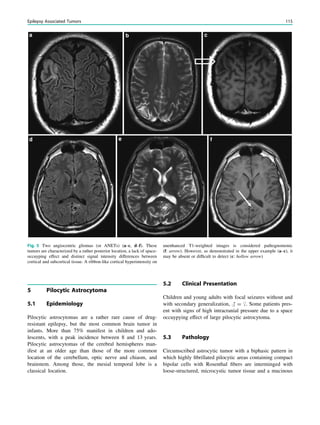

Fig. 1 Digital photogram of the brain surface before placement of a

subdural 8 9 8 grid. A second photogram was taken after grid

placement and digitally replaced by a schematic drawing detailing the

results of electrical stimulations and ictal/ intraictal EEG activity. Blue

grid contacts represent the eloquent zone, which is the motor cortex in

this case. The black area represents the epileptogenic lesion, defined

as the radiographic lesion that causes the seizures. The yellow area is

the seizure onset zone, defined as the area from which the clinical

seizures are generated. The seizure onset zone is often, but not

necessarily, congruent with the epileptogenic zone, defined as the

cortex area indispensable for the generation of seizures